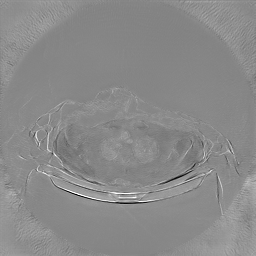

To assess the uncertainty of our method, we performed multiple reconstructions using different random seeds. As shown in Fig. 3, the ground truth and representative sampled images are presented in Fig. 3(a) and (b–d), respectively. The mean reconstruction and pixel-wise standard deviation across runs are displayed in Fig. 3(e) and (f). Only minimal differences are observed between reconstructions, indicating that I2SB produces highly consistent results. These findings confirm that, compared with classical diffusion models, I2SB substantially reduces uncertainty across repeated reconstructions.